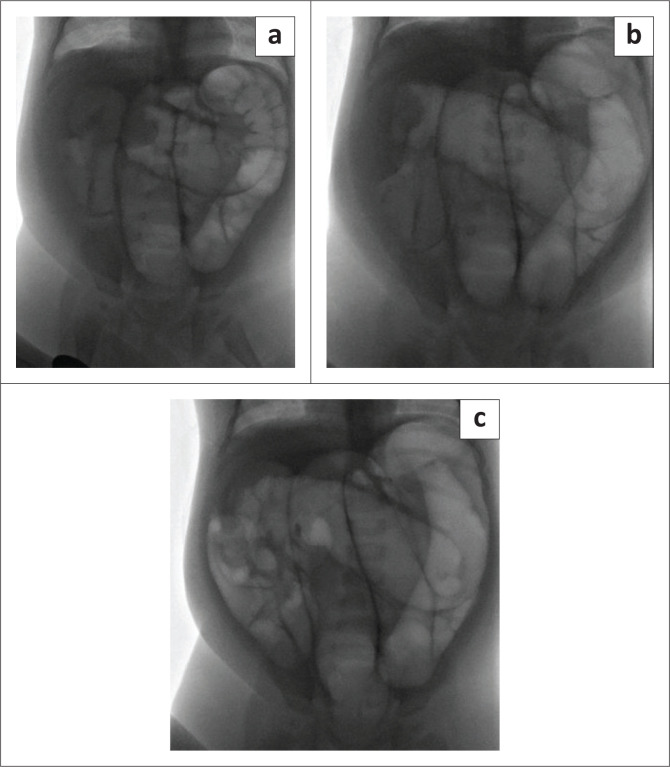

背景:肠套叠是儿童肠梗阻的常见原因,需要紧急处理以防止缺血。透视引导下的空气灌肠复位(FGAR)是无并发症病例的标准非手术治疗方法。目的:确定与小儿肠套叠FGAR结果相关的因素。方法:回顾性分析2016年11月至2022年12月在南非布隆方丹大学学术医院确诊的肠套叠患者110例。数据包括人口统计学、临床表现、实验室结果和影像学发现。结果:在110例患者中(中位年龄7个月,症状持续2天),37例主要手术治疗,73例进行FGAR尝试(31例成功,42例不成功,需要手术)。在79例手术病例中,24例采用手工复位而不切除。FGAR不成功与低龄(p = 0.0249)、脱水(p = 0.0299)、腹水(p = 0.0172)、超声显示外壁肠套叠直径增大(p = 0.0026)显著相关。结论:在这个南非队列中,不成功的FGAR与年轻、脱水、腹水和超声显示的较大的肠套叠大小有关。在资源有限的情况下,早期识别和常规超声使用对于提高非手术结果和减轻手术负担至关重要。贡献:本研究确定了低资源环境下FGAR失败的预测因素,为临床决策提供了信息,并解决了中低收入国家肠套叠管理文献中的空白。

Results: Among 110 cases (median age 7 months, symptom duration 2 days), 37 were primarily surgically managed, while 73 underwent FGAR attempts (31 successful, 42 unsuccessful, requiring surgery). Of the 79 surgical cases, 24 had manual reduction without resection. Unsuccessful FGAR was significantly associated with younger age (p = 0.0249), dehydration (p = 0.0299), ascites (p = 0.0172), and increased outer wall intussusception diameter on ultrasound (p = 0.0026).

Conclusion: In this South African cohort, unsuccessful FGAR was linked to younger age, dehydration, ascites, and larger intussusception size on ultrasound. Early recognition and routine ultrasound use are critical in resource-limited settings to enhance non-surgical outcomes and reduce surgical burden.